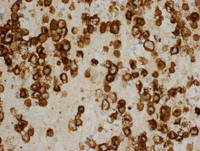

Figure 7: EBER & LANA in Primary Effusion Lymphoma

Both EBER (left) and HHV8 (right) are positive in the lymphoma cells.